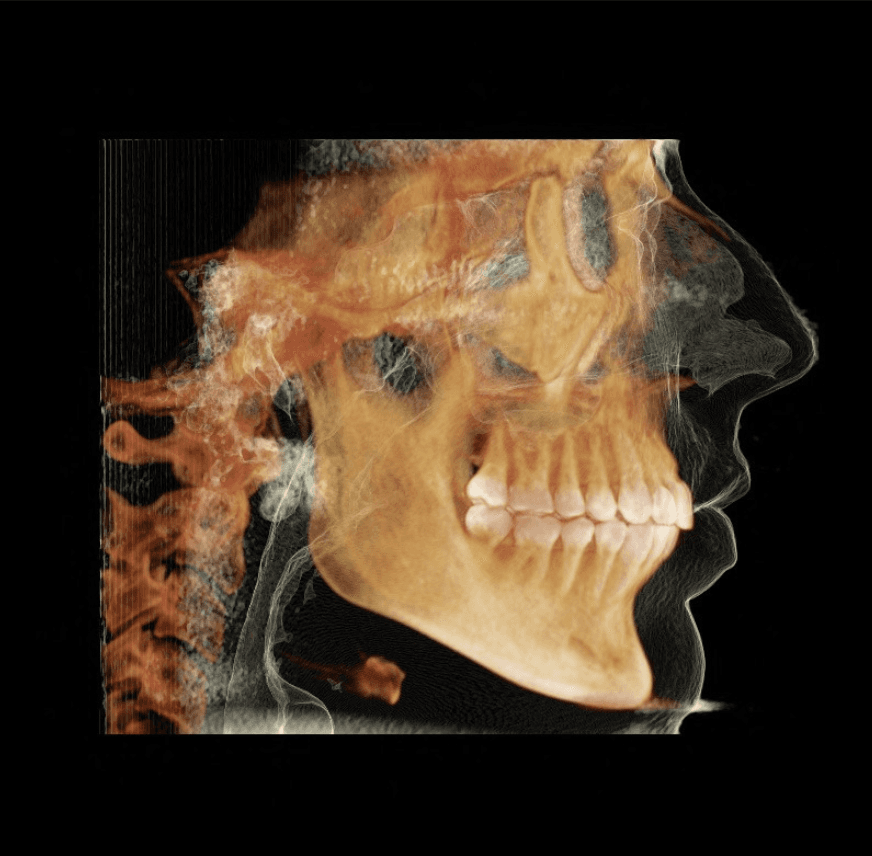

X-RAYS